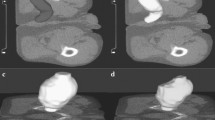

Eighteen algorithmically generated-perturbations, which simulated variations in image noise levels (σ, 2σ, 3σ, 5σ), image rotation [both CT image and the corresponding pancreas segmentation mask by 45° and 90° in axial plane], voxel resampling (isotropic and anisotropic), gray-level discretization [bin width (BW) 32 and 64)], and pancreas segmentation (sequential erosions by 3, 4, 6, and 8 pixels and dilations by 3, 4, and 6 pixels from the boundary), were introduced to the original (unperturbed) test subset (n = 128; 45 pre-diagnostic CTs, 83 control CTs with normal pancreas). Radiomic features were extracted from pancreas masks of these additional test subsets, and the model's performance was compared vis-a-vis the unperturbed test subset.